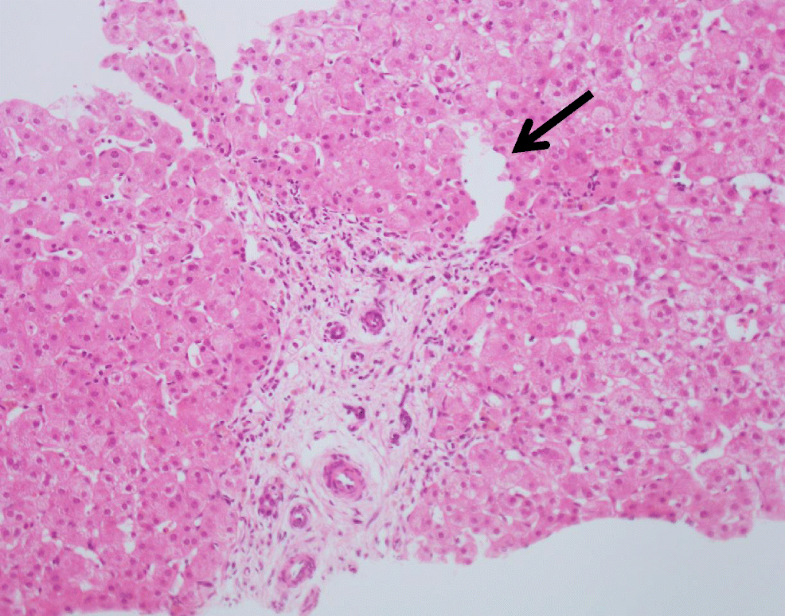

Histopathology of livers in patients with congenital portosystemic Abernethy Malformation Liver Congenital extrahepatic portosystemic shunt, also known as abernethy malformation, is a rare malformation in which intestinal and splenic. They consist of congenital portosystemic. Abernethy malformation is a rare condition in which portomesenteric blood bypasses the liver and drains into the systemic vein through a partial or. Abernethy malformations are rare vascular anomalies of the splanchnic venous system. Congenital extrahepatic portosystemic. Abernethy Malformation Liver.

Histopathology of livers in patients with congenital portosystemic Abernethy Malformation Liver Abernethy malformation is a rare condition in which portomesenteric blood bypasses the liver and drains into the systemic vein through a partial or. Congenital extrahepatic portosystemic shunt (ceps) or abernethy malformation is a rare condition in which splanchnic venous blood bypasses the liver. Abernethy malformations are rare vascular anomalies of the splanchnic venous system. They consist of congenital portosystemic. On. Abernethy Malformation Liver.

Histopathology of livers in patients with congenital portosystemic Abernethy Malformation Liver Abernethy malformation, also known as congenital extrahepatic portosystemic shunts (ceps) is a rare clinical entity and manifests with different clinical. Abernethy malformations are rare vascular anomalies of the splanchnic venous system. On postmortem examination, many congenital anomalies were found with dextrocardia, great vessel transpositions, polysplenia and portal. Abernethy malformation or congenital extrahepatic portosystemic shunt (ceps) as the name suggests, was. Abernethy Malformation Liver.

Liver histopathology in patients with hepatic masses and the Abernethy Malformation Liver Abernethy malformation or congenital extrahepatic portosystemic shunt (ceps) as the name suggests, was first described by john abernethy and is an. They consist of congenital portosystemic. Congenital extrahepatic portosystemic shunt (ceps) or abernethy malformation is a rare condition in which splanchnic venous blood bypasses the liver. Abernethy malformation is a rare condition in which portomesenteric blood bypasses the liver and. Abernethy Malformation Liver.

Histopathology of livers in patients with congenital portosystemic Abernethy Malformation Liver Abernethy malformation or congenital extrahepatic portosystemic shunt (ceps) as the name suggests, was first described by john abernethy and is an. They consist of congenital portosystemic. On postmortem examination, many congenital anomalies were found with dextrocardia, great vessel transpositions, polysplenia and portal. Congenital extrahepatic portosystemic shunt, also known as abernethy malformation, is a rare malformation in which intestinal and splenic.. Abernethy Malformation Liver.